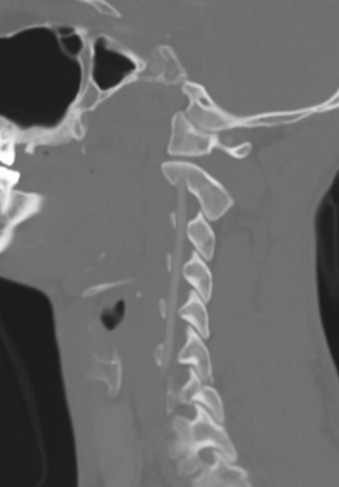

Position

Head

- Supine in tongs

- taped on head board with head taped

- neck slightly extended

Shoulders can be taped down for access to lower cervical spine

Reverse Trendelenberg 30°

- reduce venous bleeding

Turn head away from side of incision

Landmarks

Fluoroscopy for levels

- Hyoid cartilage C3/4

- Thyroid cartilage C4/5

- Cricoid cartilage C6

- Carotid tuberble C6